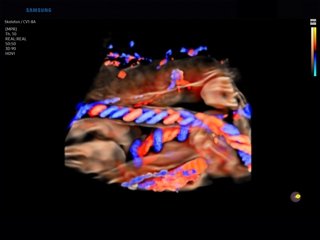

Atlas of ultrasound images (pg. 4)

The atlas of echograms is created for demonstrating the capabilities of Samsung Medison ultrasound scanners. The main part of ultrasound images is received from Korea, new echograms - from users of Samsung Medison scanners in Russia: institutes, diagnostic medical centres and private practicing doctors. The material is recommended for specialists of ultrasound diagnostics.